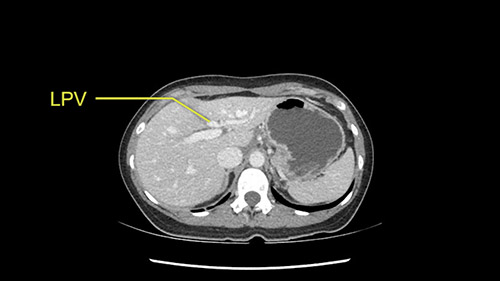

So the issue with regards to resection. A left sided tumor. I believe I can see the falciform ligament right here so we’re looking at a resection of Segments 2, 3 of the left lobe of the liver. The left portal vein is right there. I think we’ll be wiser to take the left portal vein and therefore get well into Segment 4 and do a left hemihepatectomy. Certainly, one does not need to take the middle hepatic vein; it’s miles from the tumor.

So I have to say that I would do this open, not laparoscopically because of the size of the tumor itself. Upper abdominal incision. Almost certainly, we’d be able to flip this very exophytic lesion up. Intraoperative ultrasound will show the relationship of the tumor and the left portal vein but the dissection at the base of the liver, as I look at things here, I can see the left hepatic artery which sneaks up to the left of the portal vein, should be out of harm’s way so I can take the Segment 2-3 left hepatic artery. The left portal vein is somewhat compressed. But by the time you pull the liver up a bit, you’ll be able to pull that left portal vein out to length and get a good margin on it.

Now let’s look at some specific anatomical points for planning this surgery. First thing you see when you see a left hemihepatectomy is that where is the left portal vein and the right portal vein branching? And what is the stump of the left portal vein available for you for ligation? In this particular case, you’ll find that there’s overhanging of the tumor but left portal vein pedicle is sufficiently available for us for ligation.

Once you identify the inflow of the left portal vein and the hepatic artery, its always a good idea to ensure that the bile duct is also carefully seen and preserved. The problem with the bile duct is it is thin and it might have a biliary variation which you are not appreciating on a CT scan. If there is a biliary variation, one has to be very careful not to injure the right ductal system and when you are resecting the left lobe of the liver. This is particularly true because you are having an overhanging tumor and that can distort the anatomy so one has to be careful and slow down when you are trying to ligate or identify the biliary system. It’s a good idea just to loop up the vessels, identify them and then ligate them only when you are certain that you are preserving the vasculature to the right side. I’ll prefer to ligate the inflow at this point of time. The left hepatic artery and the left portal vein to be ligated.